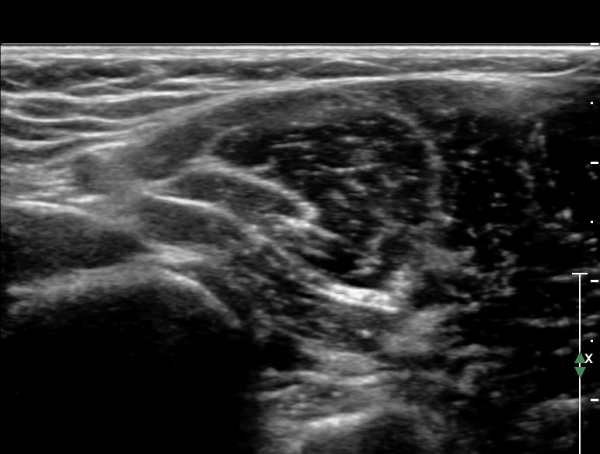

Á¤Á߽Űæ Á¾´Ü¸é°Ë»ç¿¡¼­ ȸ³»±Ù ¿ä°ñµÎ ±â½ÃºÎ¿¡¼­ Á¤Á߽ŰæÀÇ ±¹¼ÒÀû ¾Ð¹Ú°ú Ç¥ÃþÀ¸·Î ÀüÀ§°¡

°üÂûµÇ°í ¾Ð¹ÚÀÇ ±ÙÀ§ºÎ¿¡¼­´Â Á¤Áß½Å°æ ºÎÁ¾ÀÌ °üÂûµÊ(»çÁö 3).

ÀÌ·± º¯È­´Â °ÇÃø(»çÁø 6)°ú ºñ±³ÇÏ¸ç ¶Ñ·ÇÇÔ.